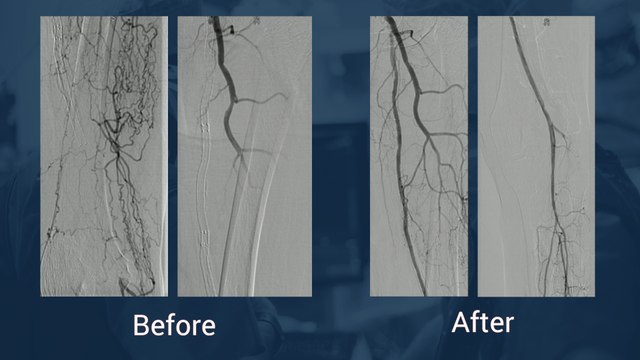

Extensive SFA occlusion/calcification

Uploaded: July 18, 2013 Views: 4